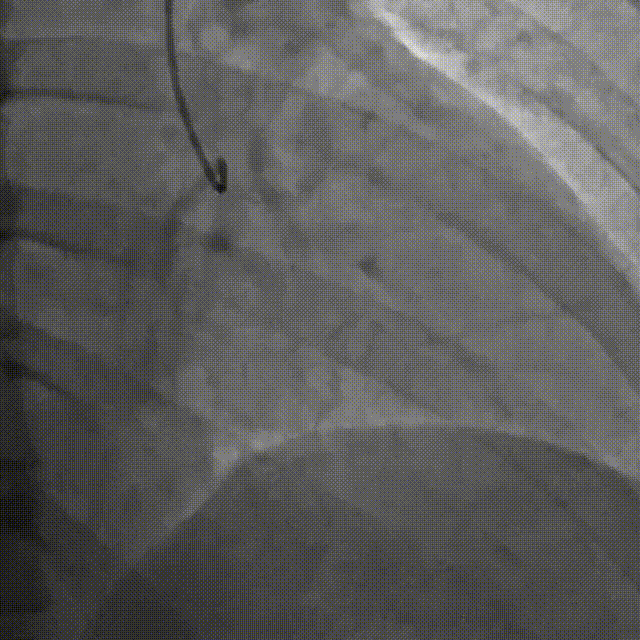

Corsair135辅助下先后尝试使用P200/G3导丝未能突破近端纤维帽,最终CP12突破后进入血管结构内,同时进行多角度确认。

尝试调整导丝重回真腔未成功,直接使用XTA导丝knuckle。

跟进corsair并交换LP球囊后,先后尝试G3/CP12/8-20等导丝穿刺均失败。

直接尝试逆向,RCA中段3.0*10切割后,使用Finecross150+SUOH03通过心外膜逆向进入LAD,FC轻松跟进。